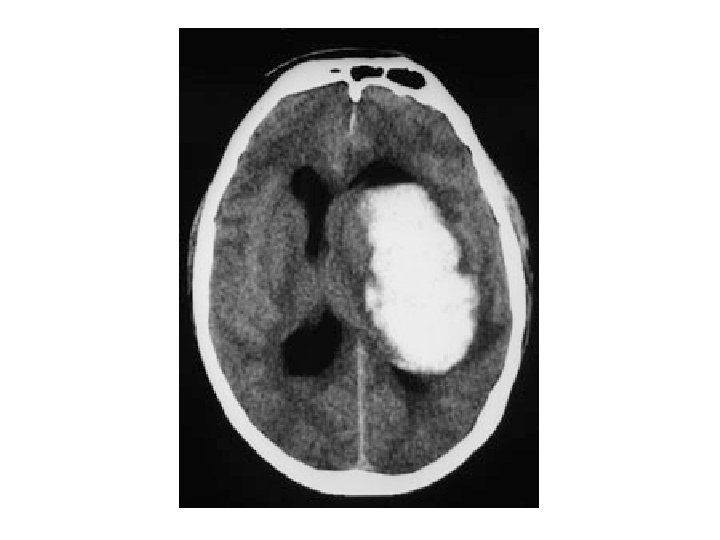

Hematoma intracerebral Colección hemática dentro del parénquima encefálico producido por la rotura de una arteria o arteriola cerebral. 50% topografía profunda, 35% lobares, 10% cerebelosos, 5% troncoencefálicos. Clínica inespecífica: Cefalea, náuseas, vómitos… Déficit neurológico. Alto índice de mortalidad.

Ictus hemorrágico Hemorragia intracerebral (HIC). Hemorragia subaracnoidea (HSA). Hematoma subdural. Hematoma epidural.

Clasificación ICTUS ISQUÉMICO (80%): Ø Clasificación clínica: • Accidente isquémico transitorio (AIT). • Infartos (Clasificación de Oxford) Ø Clasificación etiológica: • Aterotrombótico. • Cardioembólico. • Lacunar. • De causa inhabitual. • De etiología indeterminada. ICTUS HEMORRÁGICO (20%): • • Hematoma intraparenquimatoso. Hemorragia subaracnoidea (HSA). Hematoma subdural. Hematoma epidural.